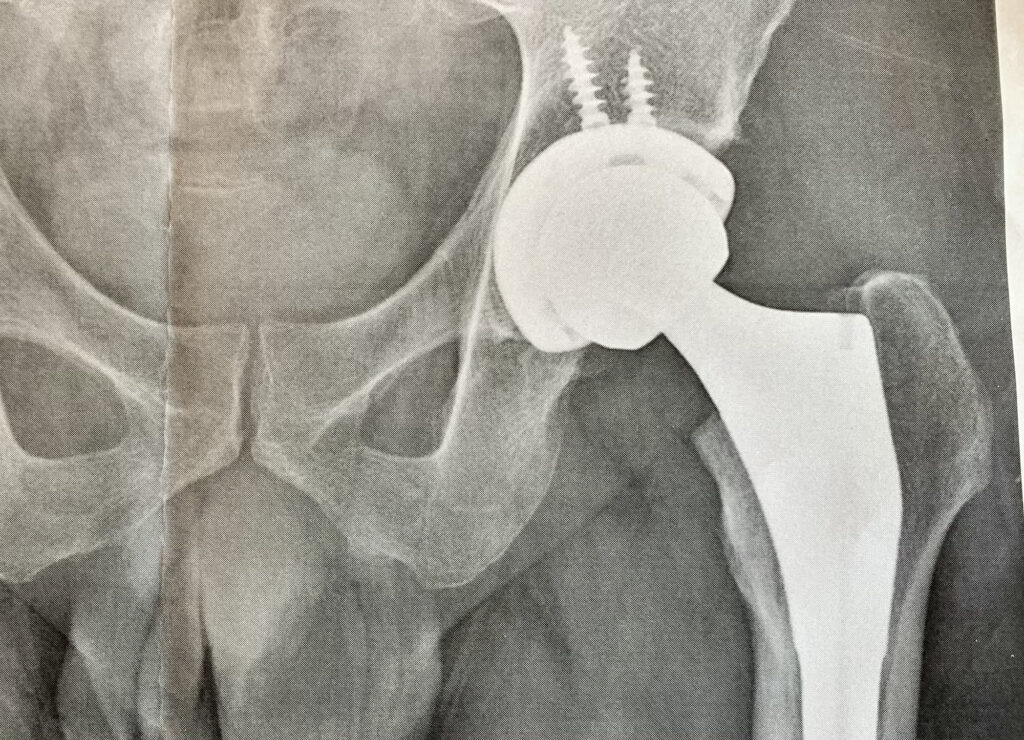

Wさん: よろしくお願いします。新卒で住宅メーカーに入社した後、かねてから志望していた医療機器メーカーに転職し、営業として股関節や膝関節のインプラントを担当しています。